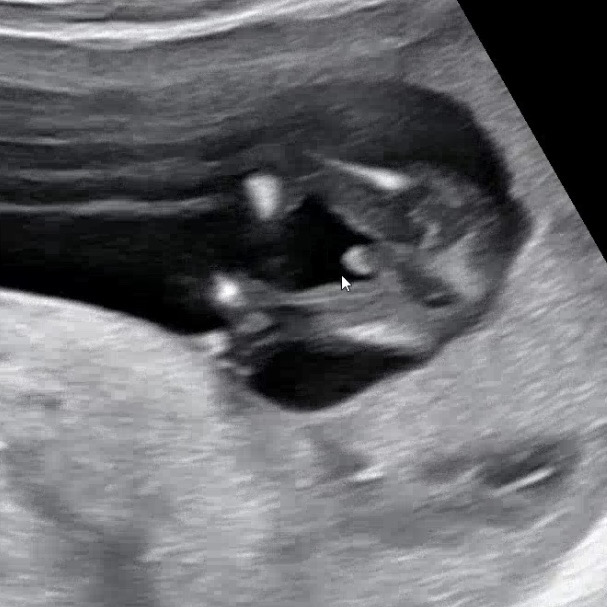

2026년 3월 베동

/ 성별질문

13주차 아들 확정~

12주차 때 실시한 니프티검사 결과 들으러 병원 갔다가 확정받고오는 길이에요 ㅎㅎ 첫째사 아들이면 좋겠다고 생각했는데 진짜 아들이네요! 하핫